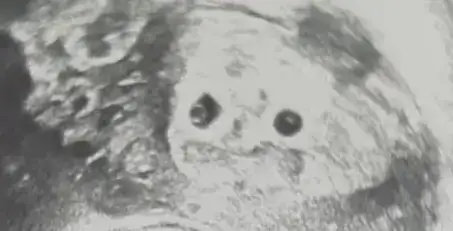

Ben hala anlayamadım kafam basmadi vajinal bakıldı sizce nedirŞunu şuraya koyayım kıslar kendiniz de anlayabilirsiniz 9. Haftadan sonra. Nub teorisinin ramziye göre tutma olasılığı daha fazla bildiğim kadarıyla

9 haftalık olan ultrasondan bahsediyorsun dimi? Canım ramzi teorisi 6-8 haftalık arasında bakılıyor dediğim gibi. Bebek büyüdükçe sol ya sağ kavramı değişiyor hareketlendiği için anlayamazsın. 9. Haftadan sonra da hareketleniyor zaten ramzi teorisini anlayamayız o yüzden nub daha sağlıklı oluyor o haftalarda .Hepsini anlamıştım burada kafam karıştı, bebek ortada olsa da sağa doğru duruyor. Plesantası da o tarafta değil mi? beni aydınlatır mısın

Seninki nub bakmak için erken zaten ramzi teorisine göre kız vajinal bakıldıysaBen hala anlayamadım kafam basmadi vajinal bakıldı sizce nedir